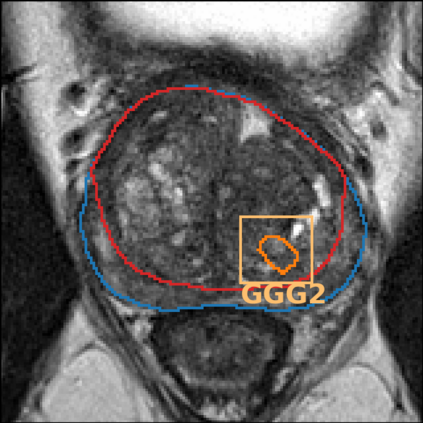

The emergence of multi-parametric magnetic resonance imaging (mpMRI) has had a profound impact on the diagnosis of prostate cancers (PCa), which is the most prevalent malignancy in males in the western world, enabling a better selection of patients for confirmation biopsy. However, analyzing these images is complex even for experts, hence opening an opportunity for computer-aided diagnosis systems to seize. This paper proposes a fully automatic system based on Deep Learning that takes a prostate mpMRI from a PCa-suspect patient and, by leveraging the Retina U-Net detection framework, locates PCa lesions, segments them, and predicts their most likely Gleason grade group (GGG). It uses 490 mpMRIs for training/validation, and 75 patients for testing from two different datasets: ProstateX and IVO (Valencia Oncology Institute Foundation). In the test set, it achieves an excellent lesion-level AUC/sensitivity/specificity for the GGG$\geq$2 significance criterion of 0.96/1.00/0.79 for the ProstateX dataset, and 0.95/1.00/0.80 for the IVO dataset. Evaluated at a patient level, the results are 0.87/1.00/0.375 in ProstateX, and 0.91/1.00/0.762 in IVO. Furthermore, on the online ProstateX grand challenge, the model obtained an AUC of 0.85 (0.87 when trained only on the ProstateX data, tying up with the original winner of the challenge). For expert comparison, IVO radiologist's PI-RADS 4 sensitivity/specificity were 0.88/0.56 at a lesion level, and 0.85/0.58 at a patient level. Additional subsystems for automatic prostate zonal segmentation and mpMRI non-rigid sequence registration were also employed to produce the final fully automated system. The code for the ProstateX-trained system has been made openly available at https://github.com/OscarPellicer/prostate_lesion_detection. We hope that this will represent a landmark for future research to use, compare and improve upon.